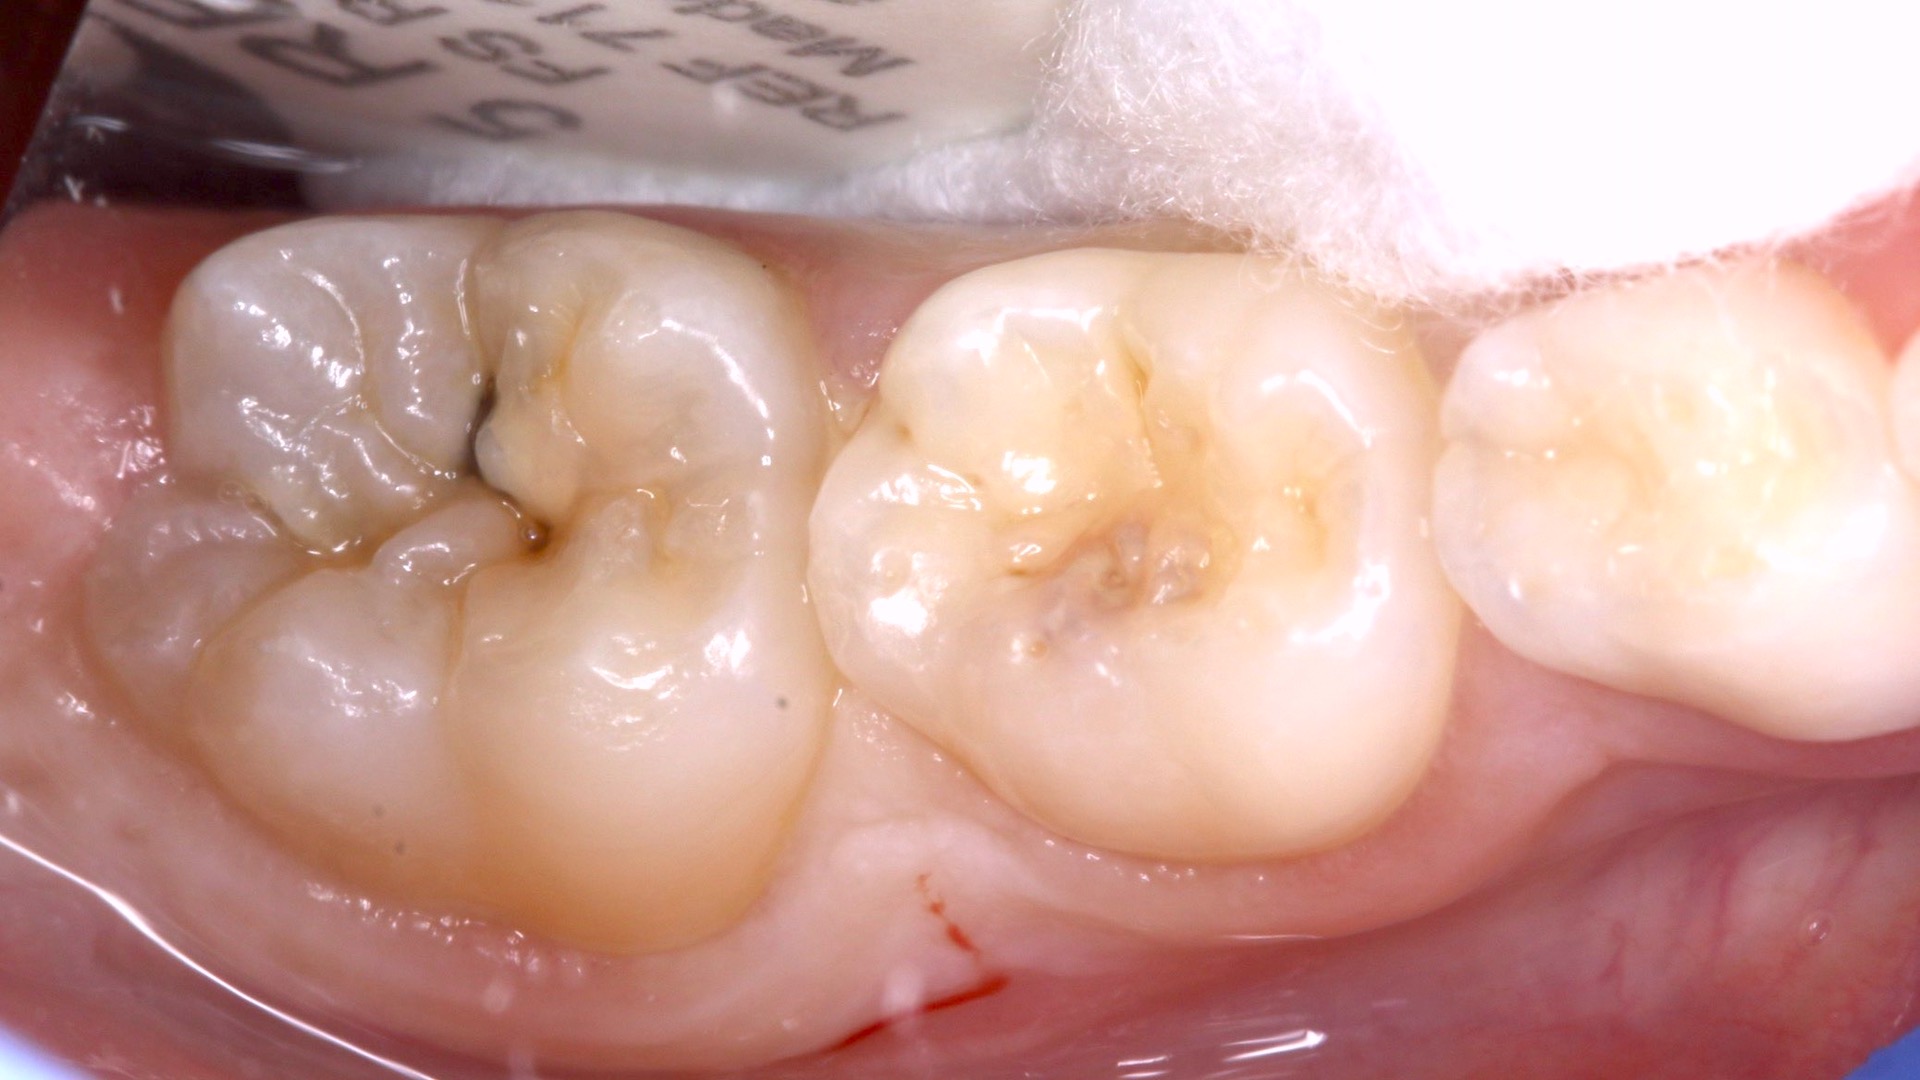

Por la severidad de la lesión, sin una cavidad evidente, se decide realizar una remoción de esmalte con alta rotación utilizando fresas diamantadas con la finalidad de acceder a la dentina cariada con instrumentos manuales, complementados con un agente enzimático a base de papaína (Papacarie Duo, Formula & Ação) (Fig. 3).

Fig. 3. La remoción de esmalte con fresas diamantadas para acceder a la dentina cariada con instrumentos manuales se complementó con la aplicación de un agente enzimático a base de papaína.

Antes de proceder con la limpieza de la cavidad, se toma una impresión de la anatomía con un material de barrera gingival (Gingival Barrier, SDI Ltd.) fijado en un micro-aplicador (Fig. 4), de forma que se pueda copiar la anatomía existente mediante la técnica del estampado oclusal (Fig. 5). Tras realizar la apertura de la cavidad (Fig. 6) se inicia la remoción selectiva del tejido cariado con una estrategia químico-mecánica (Fig. 7) hasta llegar a DENTINA FIRME en la base y dura en la periferia de la cavidad (Fig. 8) bajo aislamiento relativo utilizando Optragate (Ivoclar Vivadent) y rollos de algodón, se procede a aplicar el material restaurador EQUIA Forte fil (Fig. 9).